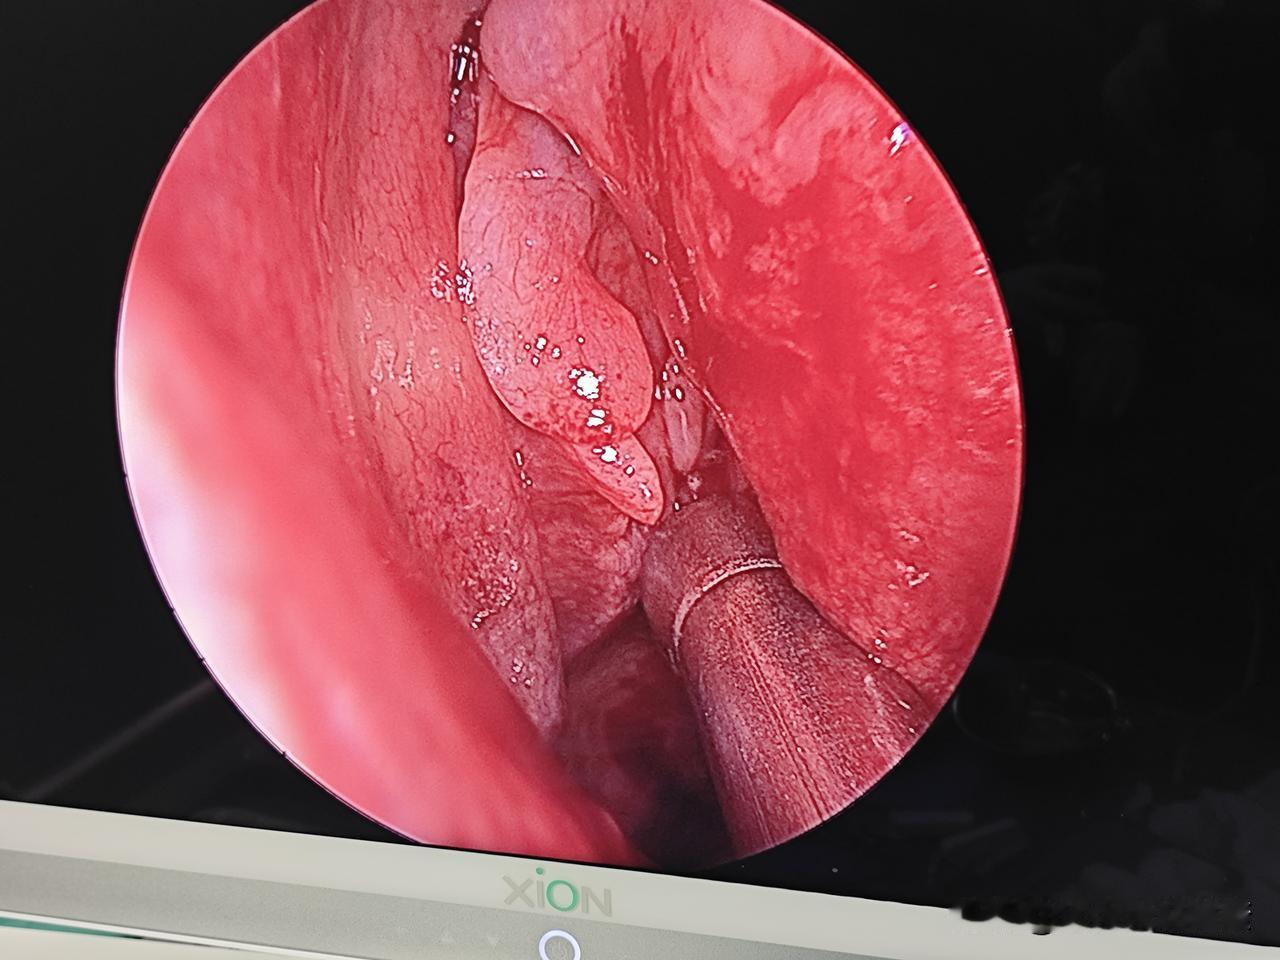

别再说声带息肉是小手术!只有耳鼻喉医生才懂这种几近崩溃的无助! 今天做完最后